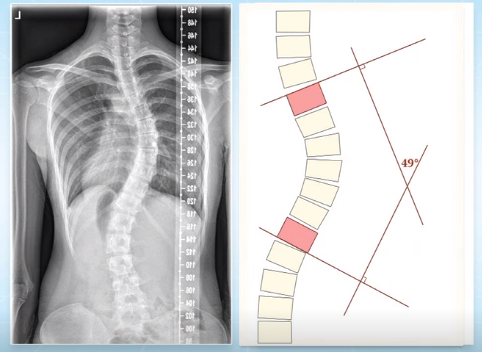

脊柱側(cè)彎的角度測(cè)量